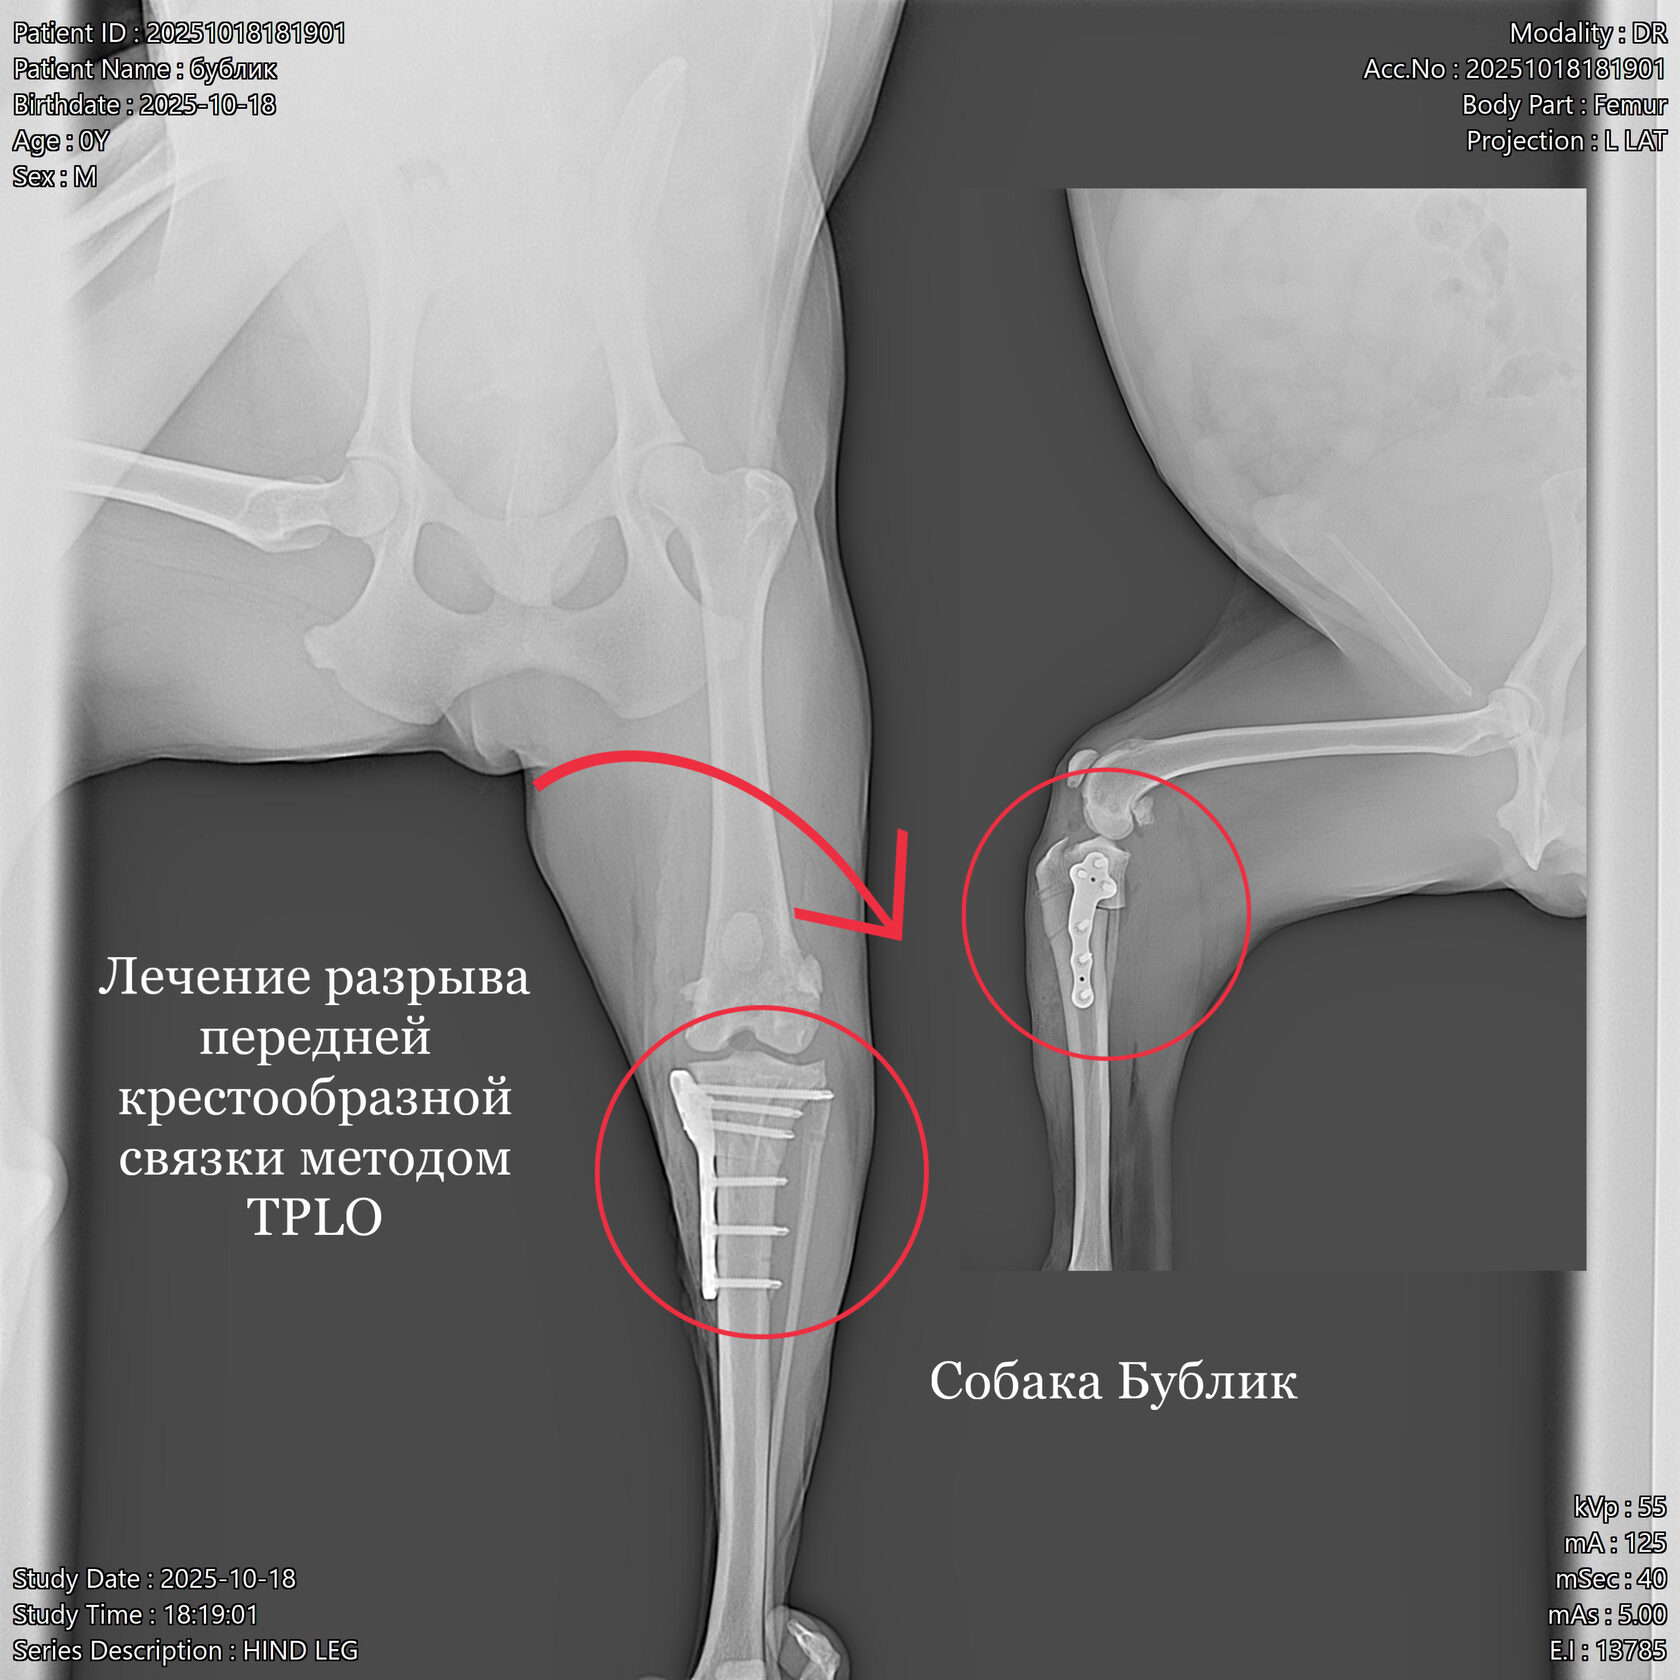

Узнайте, что делать при разрыве ПКС у собаки. Описание симптомов, диагностика (рентген, тесты), методы лечения (TPLO, латеральный шов) и реабилитация. Экспертная помощь ортопедов.

Ветеринарная травматология охватывает широкий спектр состояний: от вывихов и растяжений до сложных переломов. Ветеринар-травматолог применяет как консервативные методы (иммобилизация, медикаменты, физиотерапия), так и хирургическое вмешательство.

При сложных повреждениях используются остеосинтез, артроскопия и другие современные техники. Лечение проходит под контролем врача-анестезиолога, с учётом возраста и состояния животного.